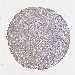

LIVER CANCER - Protein expressioni

A mouse-over function shows sample information and annotation data. Click on an image to view it in a full screen mode. Samples can be filtered based on level of antibody staining by selecting one or several of the following categories: high, medium, low and not detected. The assay and annotation is described here.

Note that samples used for immunohistochemistry by the Human Protein Atlas do not correspond to samples in the TCGA dataset.

Antibody stainingi

Antibody staining in the annotated cell types in the current human tissue is reported as not detected, low, medium, or high, based on conventional immunohistochemistry profiling in selected tissues. This score is based on the combination of the staining intensity and fraction of stained cells.

Each image is clickable and will lead to virtual microscopy that enables deeper exploration of all samples and also displays staining intensity scores, fraction scores and subcellular localization as well as patient and tissue information for each sample.

HPA046356

HPA048287

HPA050103

CAB009811

CAB032603

Staining

High

Medium

Low

Not detected

Intensity

Strong

Moderate

Weak

Negative

Quantity

>75%

75%-25%

<25%

None

Location

Nuclear

Cytoplasmic/membranous

Cytoplasmic/membranous,nuclear

Cholangiocarcinoma

Carcinoma, Hepatocellular, NOS